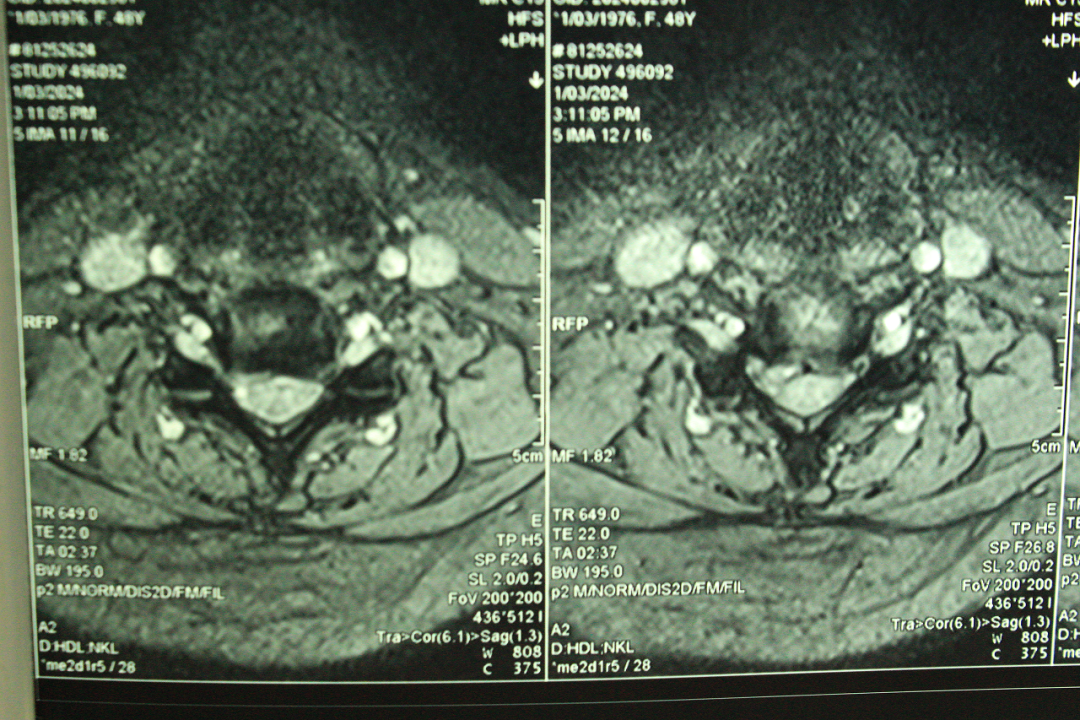

据了解,患者女性,53岁,右上肢麻木疼痛肌力减退一年加重一个月,经脊柱外科首席专家团队认真检查,CT无椎间盘钙化,MRI提示颈5/6椎间盘脱出并向下游离,初步考虑为颈5/6椎间盘突出伴神经根病,考虑选择微创手术治疗。

经过与甘肃省脊柱内镜专科联盟王想福主任会诊,病历典型,决定使用K—hole技术进行手术治疗。术后患者右上肢疼痛麻木缓解,术后第二天拔出引流管,患者情况稳定,已开始下地活动,正在积极康复中。